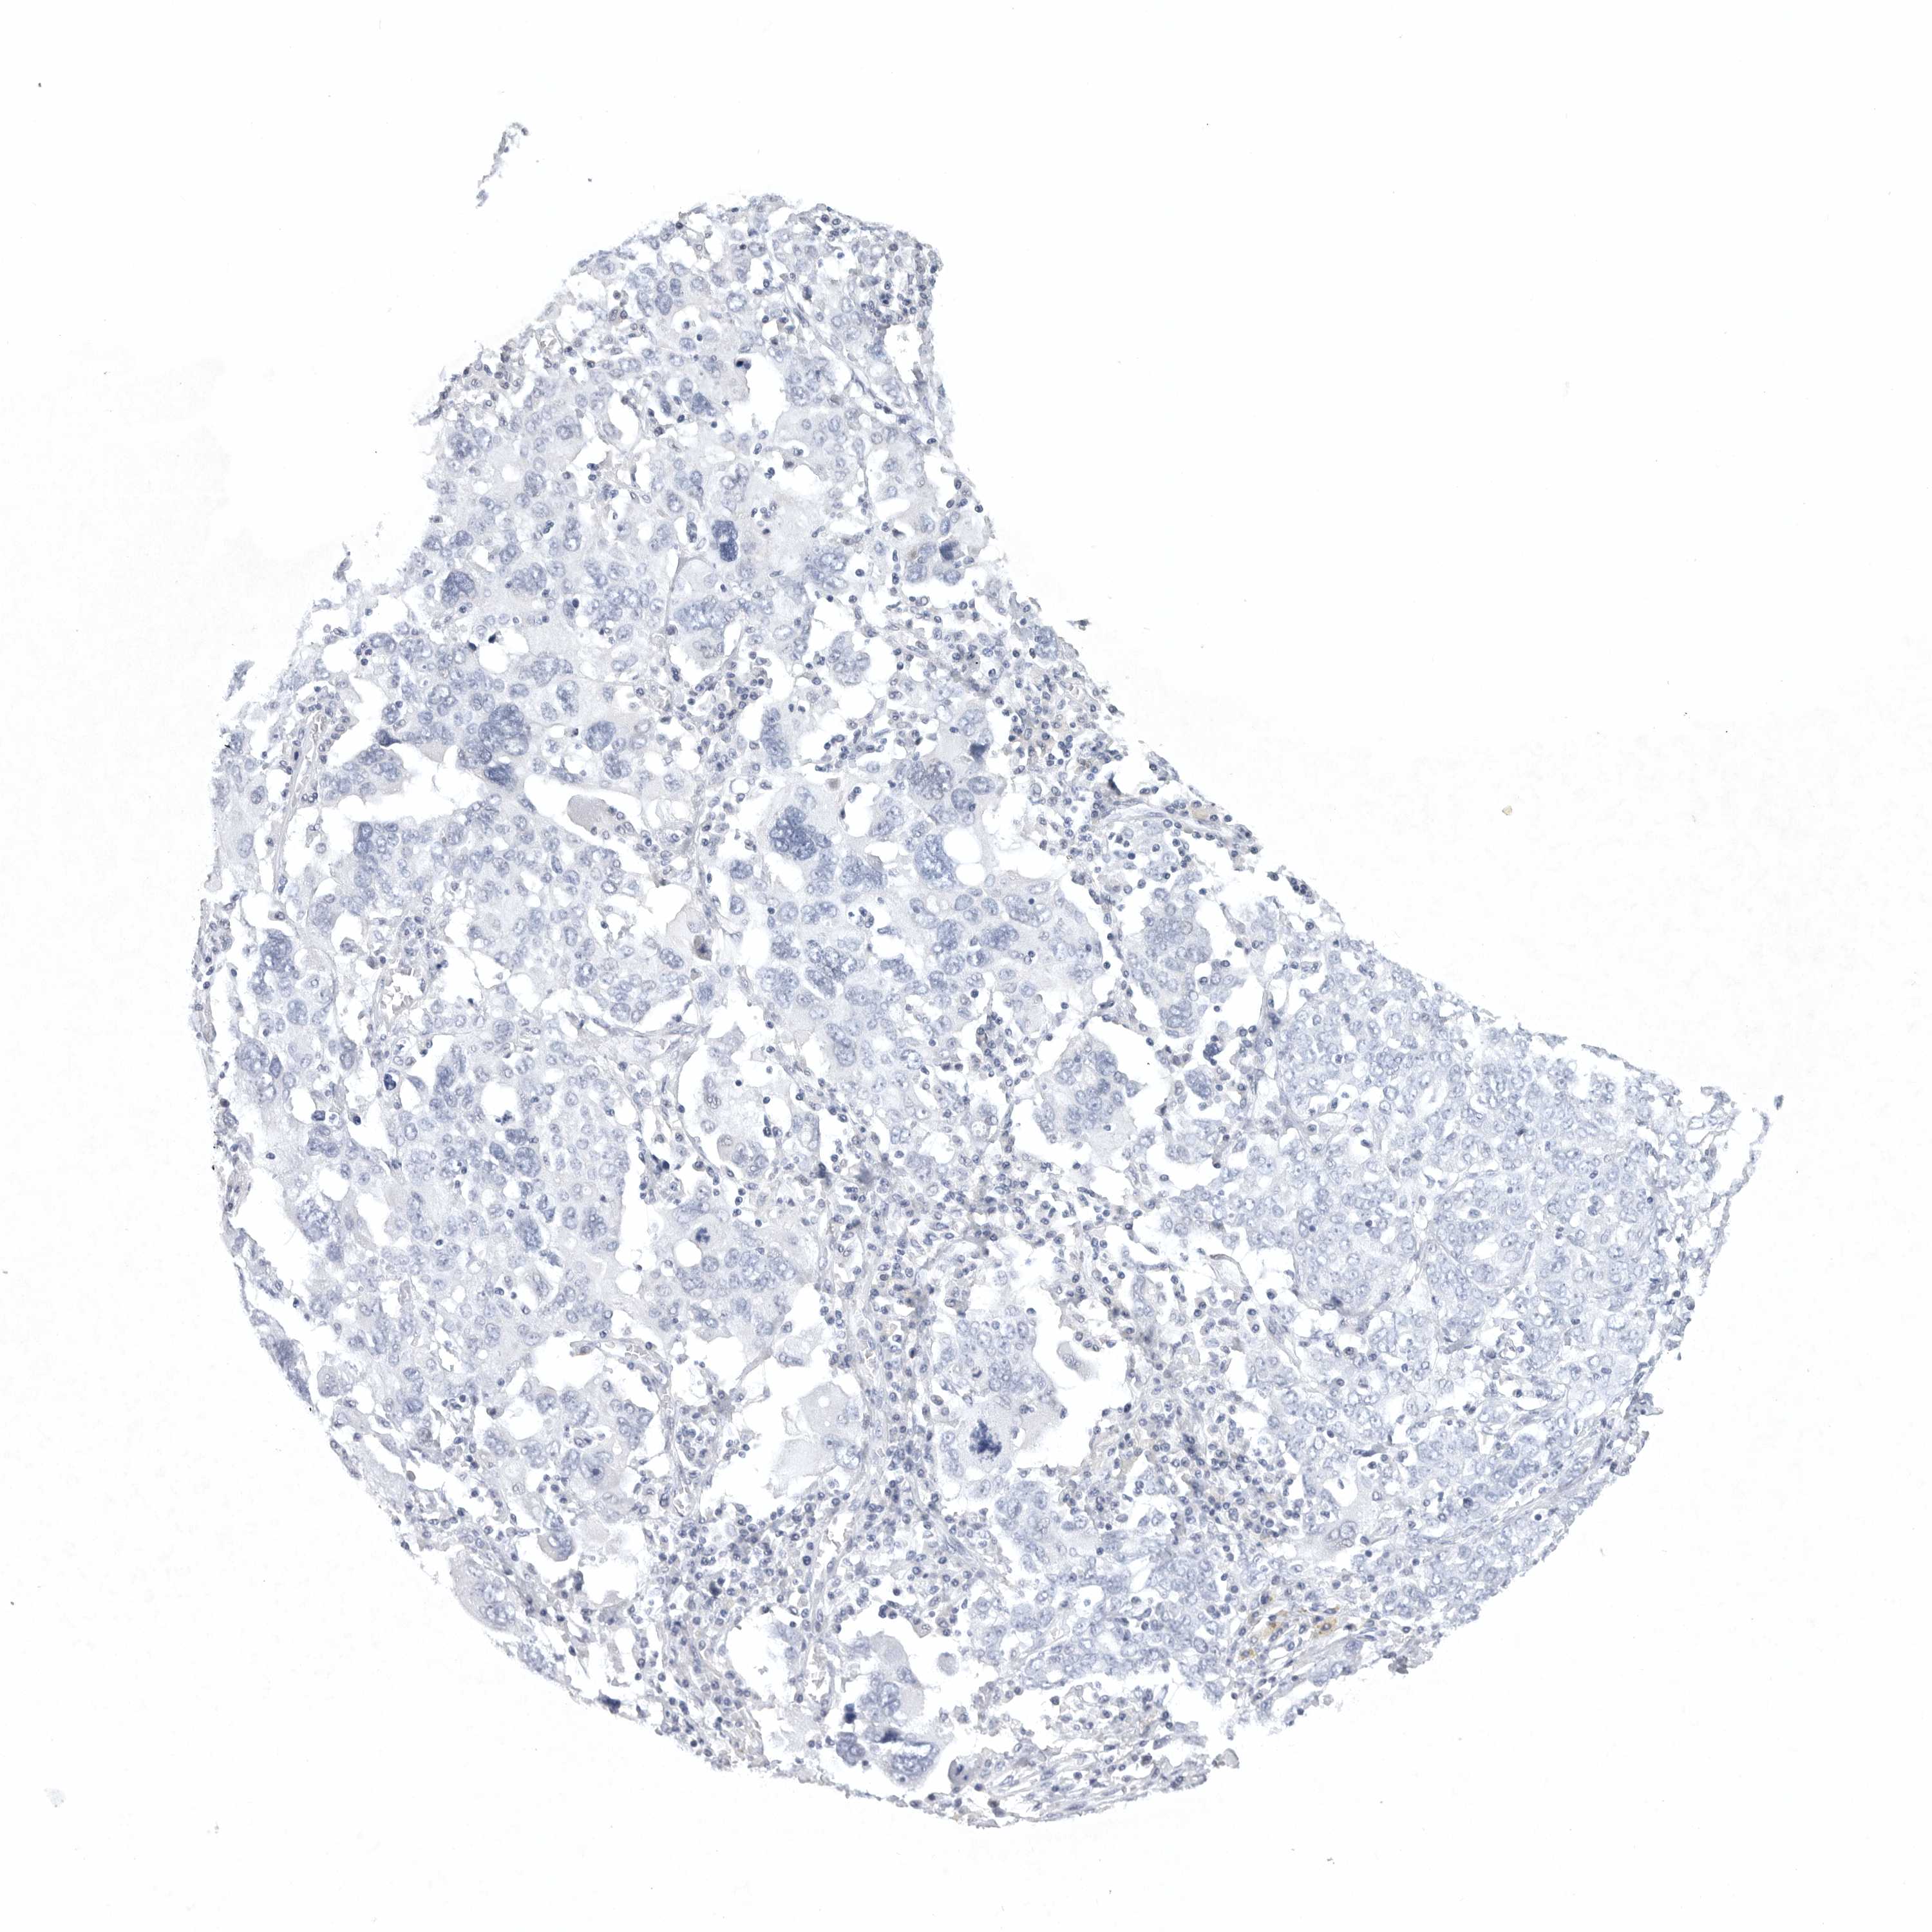

OVARIAN CANCER - Protein expressioni

A mouse-over function shows sample information and annotation data. Click on an image to view it in a full screen mode. Samples can be filtered based on level of antibody staining by selecting one or several of the following categories: high, medium, low and not detected. The assay and annotation is described here.

Note that samples used for immunohistochemistry by the Human Protein Atlas do not correspond to samples in the TCGA dataset.

Antibody stainingi

Antibody staining in the annotated cell types in the current human tissue is reported as not detected, low, medium, or high, based on conventional immunohistochemistry profiling in selected tissues. This score is based on the combination of the staining intensity and fraction of stained cells.

Each image is clickable and will lead to virtual microscopy that enables deeper exploration of all samples and also displays staining intensity scores, fraction scores and subcellular localization as well as patient and tissue information for each sample.

Antibody HPA027134

Antibody HPA027150

Antibody HPA029859

Antibody CAB022343

Staining

High

Medium

Low

Not detected

Intensity

Strong

Moderate

Weak

Negative

Quantity

>75%

75%-25%

<25%

None

Location

Nuclear

Cytoplasmic/membranous

Cytoplasmic/membranous,nuclear

Cystadenocarcinoma, serous, NOS

Carcinoma, endometroid

Cystadenocarcinoma, mucinous, NOS

Carcinoma, NOS